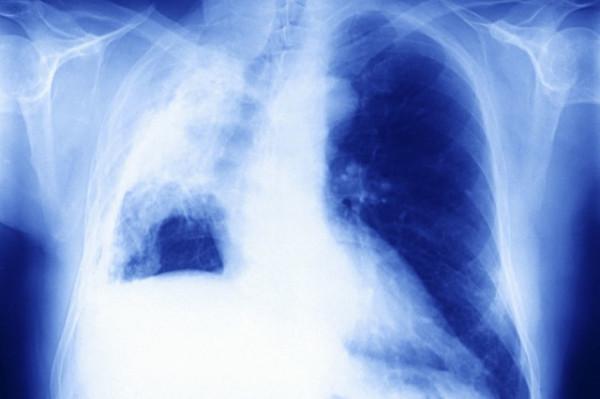

“他的胸水已經把右肺壓沒了,他昏迷很大程度上是因為右肺功能完全喪失所致的,呼吸不了,你明白嗎?

“是這樣的,如果要治療,第一步我們先處理胸水,我剛剛也說了,他現在右肺功能幾乎是喪失的,只有改善了右肺情況,才有可能下呼吸機,做後續治療。”醫生無奈的解釋道。